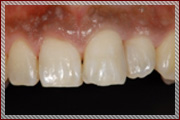

C1〜C2の治療:歯の表面と内側を削って詰める治療を行います

単に虫歯を削って詰めるといっても暗くて小さいお口の中で、

患者さまの健康な歯を傷つけずに虫歯の部分のみを取り除くことは、

非常に困難な作業です。

そのため従来の肉眼による治療では、

虫歯以外の健康な歯もたくさん削られて治療されていました。

その結果、治療後も歯がしみる、痛いなどの不快症状が残ることがあります。

当院では顕微鏡などの拡大鏡を使用することにより、

健康な歯を削らずに残し、

むし歯になってしまった部分だけを取り除いて

そこに接着材料をつかってきれいに封鎖する

MI治療(Minimum Intervention〜最小の侵襲)をおこなっております。

治療後の不快症状を最小限におさえ、なによりも従来の治療よりも歯を削らないため

患者さまの大切な歯を長持ちさせることができます。